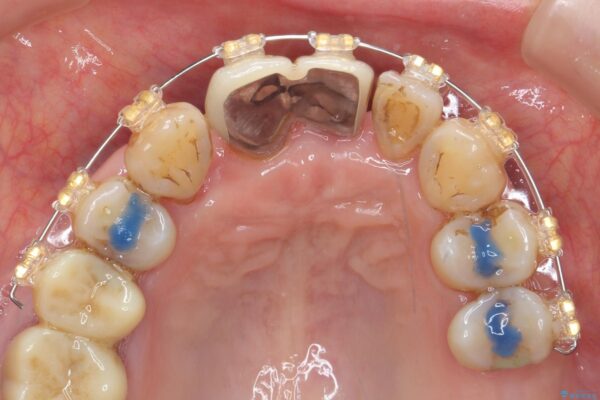

• 矯正装置:ワイヤー矯正

まず、保存の難しい歯を抜去したのち矯正治療を行い歯並びの改善、歯周ポケットを除去したことで安定した歯周環境、咬合関係を作り出すことができました。

矯正治療を事前に行ったことで全ての歯の神経を温存しセラミックブリッジを装着することができました。

治療中

歯の総合的なマネージメントを行う包括的歯科治療の実践[ 歯周病・矯正・セラミック補綴 ] 治療中画像 歯の総合的なマネージメントを行う包括的歯科治療の実践[ 歯周病・矯正・セラミック補綴 ] 治療中画像 歯の総合的なマネージメントを行う包括的歯科治療の実践[ 歯周病・矯正・セラミック補綴 ] 治療中画像 歯の総合的なマネージメントを行う包括的歯科治療の実践[ 歯周病・矯正・セラミック補綴 ] 治療中画像 歯の総合的なマネージメントを行う包括的歯科治療の実践[ 歯周病・矯正・セラミック補綴 ] 治療中画像 歯の総合的なマネージメントを行う包括的歯科治療の実践[ 歯周病・矯正・セラミック補綴 ] 治療中画像 歯の総合的なマネージメントを行う包括的歯科治療の実践[ 歯周病・矯正・セラミック補綴 ] 治療中画像 歯の総合的なマネージメントを行う包括的歯科治療の実践[ 歯周病・矯正・セラミック補綴 ] 治療中画像 歯の総合的なマネージメントを行う包括的歯科治療の実践[ 歯周病・矯正・セラミック補綴 ] 治療中画像 歯の総合的なマネージメントを行う包括的歯科治療の実践[ 歯周病・矯正・セラミック補綴 ] 治療中画像 歯の総合的なマネージメントを行う包括的歯科治療の実践[ 歯周病・矯正・セラミック補綴 ] 治療中画像